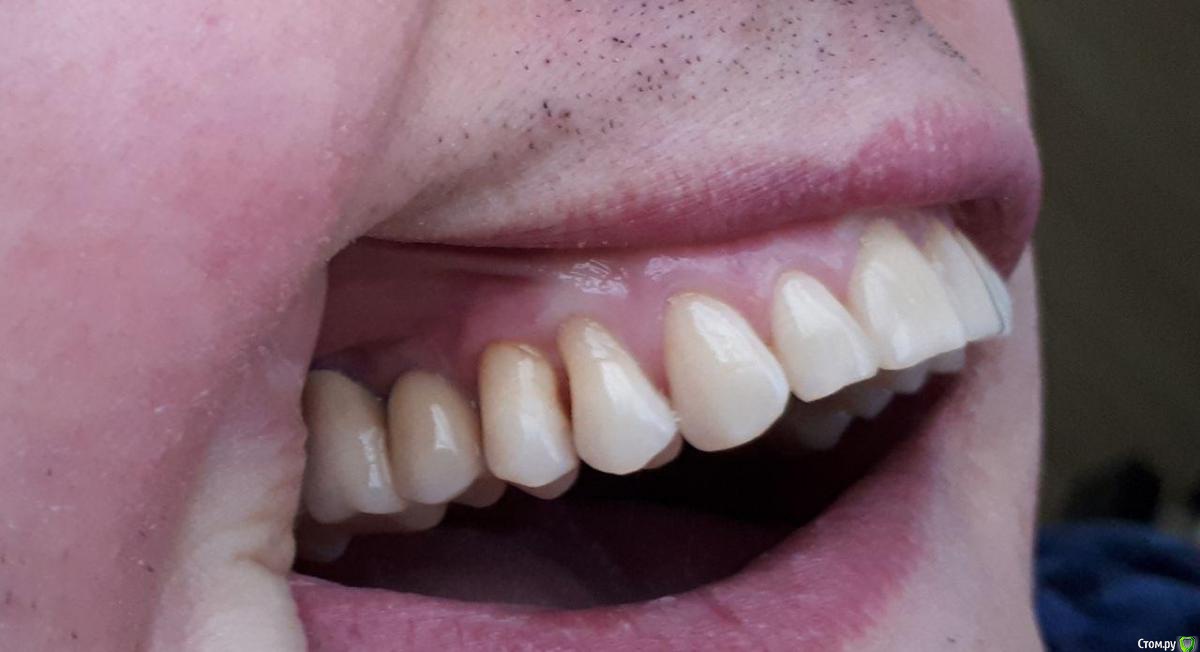

Доброго времени суток! Будьте добры, посоветуйте хорошего, опытного хирурга-пародонтолога, работающего поближе к Магнитогорску.- Челябинск, Екатеринбург, Уфа, Оренбург, Самара, который смог бы помочь мне с моей проблемой,а проблема заключается в генерализованной рецессии. Заранее Спасибо!